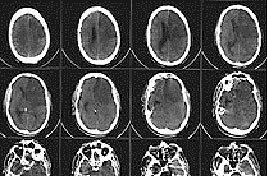

Серия КТ-снимков головного мозга, демонстрирующая ишемический инсульт в зоне кровоснабжения левых передней и средней мозговых артерий (на изображении — справа).

При компьютерной томографии (КТ) головы область гиподенсивности (пониженной плотности) у большинства больных выявляется через 12—24 ч с момента развития ишемического инсульта. При меньшей давности поражение не обнаруживается почти в половине случаев. Небольшие по размеру инфаркты мозга (инфаркты в мозговом стволе и лакунарные инфаркты) часто не дифференцируются на бесконтрастных КТ-изображениях даже на 3—4-й день заболевания (в период, когда инфаркты других локализаций визуализируются наилучшим образом), однако могут быть обнаружены при КТ с контрастированием. Проведение КТ с внутривенным контрастным усилением также показано в неясных случаях для дифференциальной диагностики.